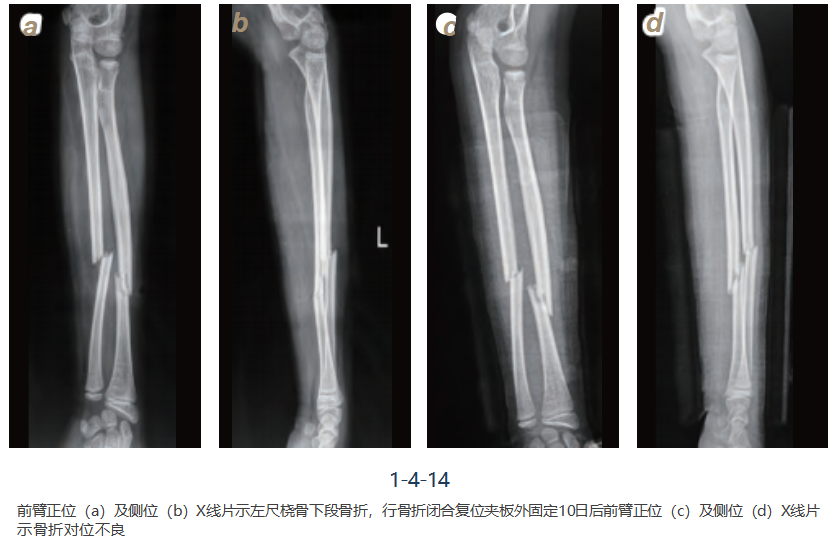

病例二

女,10岁,摔伤致左前臂肿胀、压痛、畸形、活动受限,诊断为左尺桡骨骨折,行左尺 桡骨骨折闭合复位弹性钉内固定术,术后恢复良好(图1-4-14~16)。